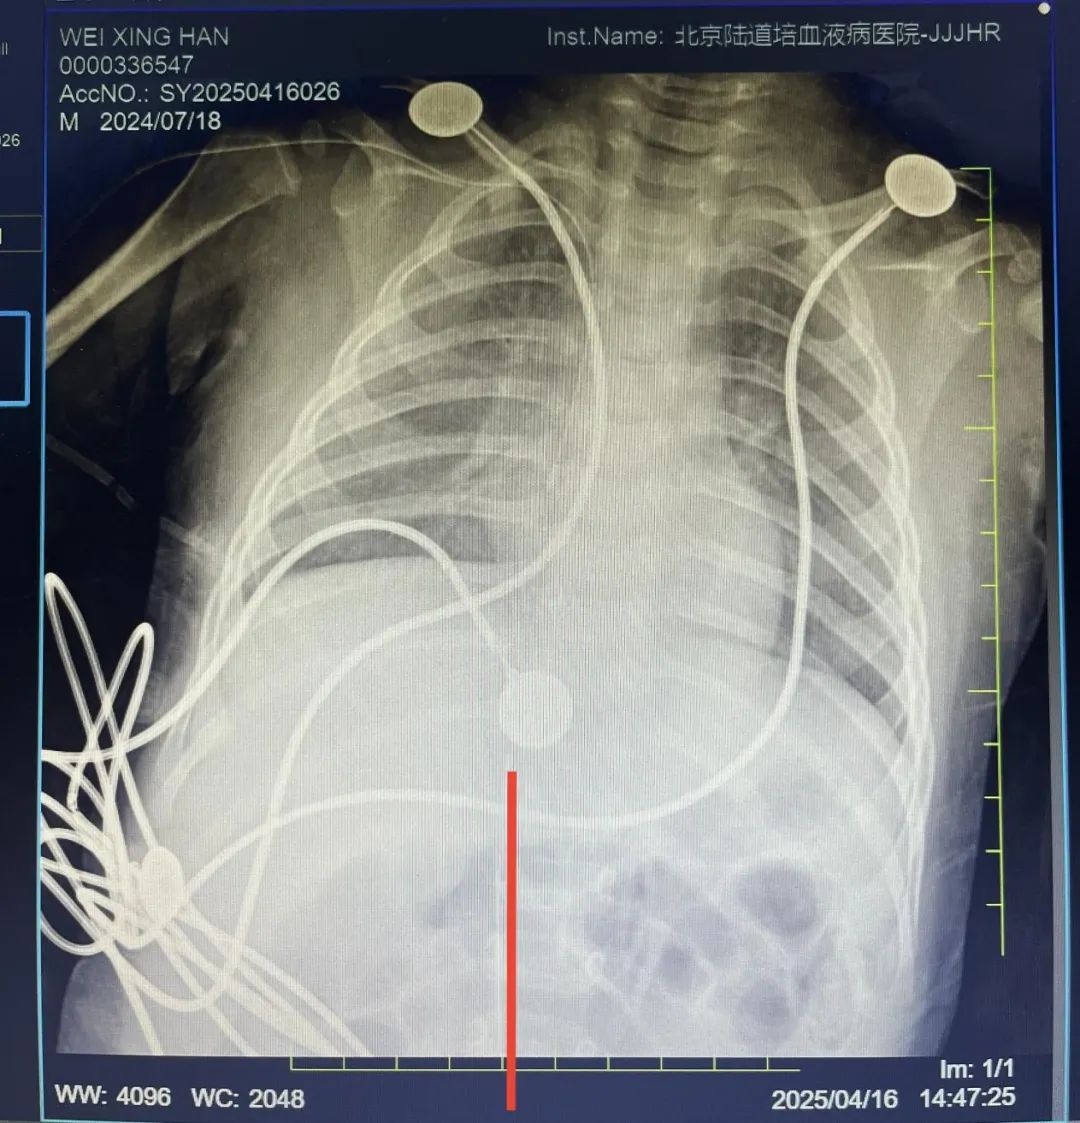

红线是下肢 PICC 的管路位置

4 月 16 日,在护理团队的全力配合下顺利完成此次置管,经影像科石玉铸主任会诊后,确定导管位置符合要求,可正常使用,此为顺义院区首例 7 月龄患儿以及首例股静脉 PICC 置管,为患儿建立了长期、安全有效的静脉通路,保障移植顺利进行。在医护团队的精心照顾和维护下,患儿各类药物及造血干细胞输入顺利,为小星星的后续治疗开辟了一条别样的「生命线」。